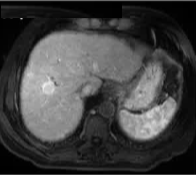

69 岁的男性患者,患有丙型肝炎相关肝硬化,其肝脏增强扫描(S8)中可见一个 22 mm 肝细胞癌结节。